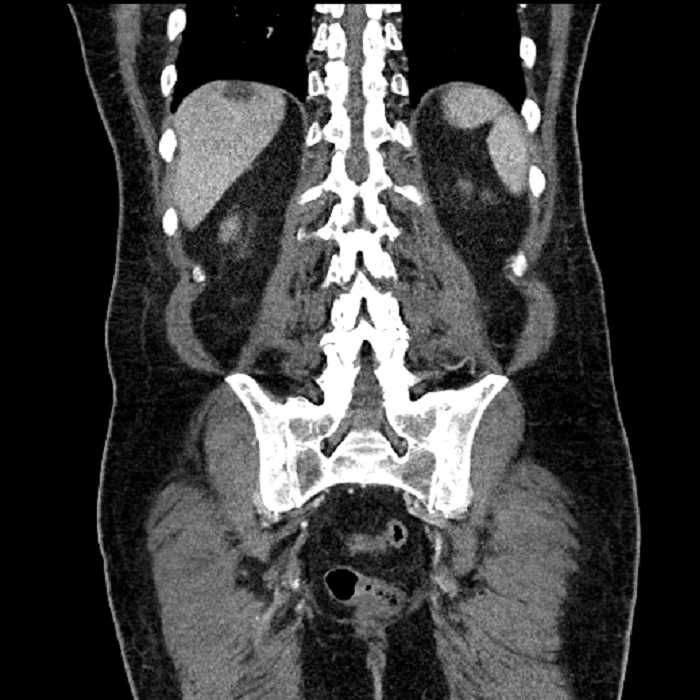

Age: 63

Sex: Male

Indication: Abdominal pain

• Large fluid density structure in hepatic segments 7 and 8 measuring 10 x 7 x 7 cm with internal septation and circumferential ill-defined low density compatible with edema

• Peripherally enhancing subcapsular collections along the anterior margin of the left hepatic lobe measuring 3 x 1 cm and 2 x 1 cm

• Clearly marginated fluid density structure in segment 7 and several other scattered tiny hypodensities, which likely represent cysts

• Hepatic abscess

Acute sigmoid diverticulitis complicated by a small contained perforation and a large abscess in the right hepatic lobe. Additional small subcapsular abscesses along the anterior margin of the left hepatic lobe.

Additionally, loss of the normal fat plane between the peridiverticular collection and adjacent thickened loops of small bowel raises the potential for an enterocolonic fistula.

• The classic CT imaging appearance is a double target sign with internal low density surrounded by an internal enhancing rim (capsule) and a low density external rim (edema)

Hepatic abscess showing the double target sign with low density internally surrounded by a thin inner enhancing rim (red arrow) and ill-defined outer low density rim (yellow arrow). Blue arrow indicates an internal septation. Red arrows: additional smaller subcapsular abscesses. Red arrow: focal contained perforation associated with diverticulitis.